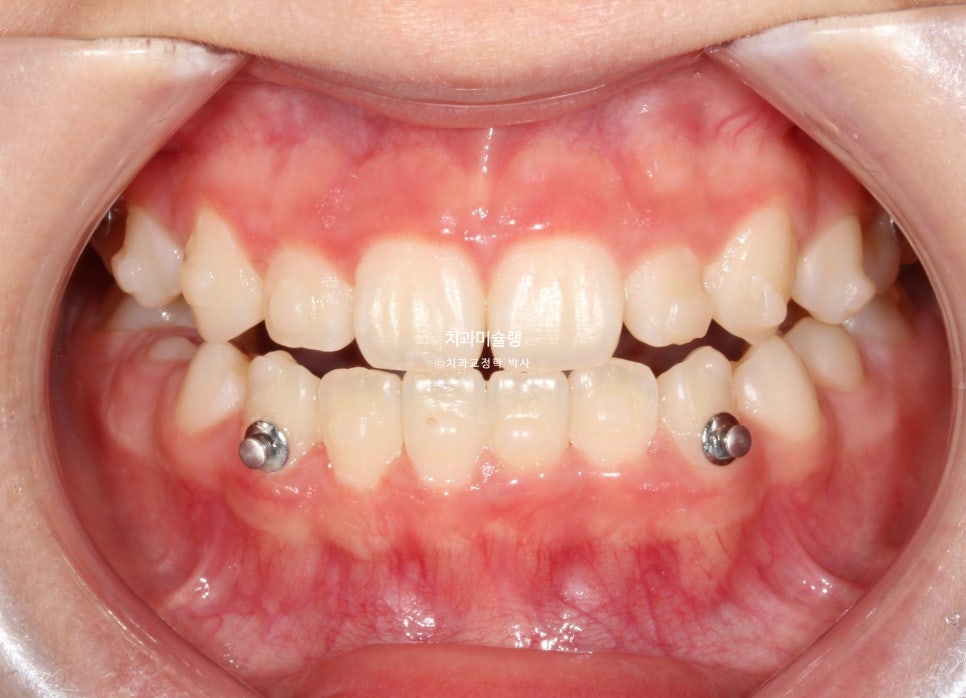

두 번째 재제작 (17개 장치)

3급 교합관계 개선을 위해 두번째 재제작에 들어갑니다.

마지막 세트 장치 갯수는 17개이며 마찬가지로 3급 고무줄을 내내 열심히 끼도록 당부했습니다.

2026년 2월, 정상교합이 달성되어 치료를 마무리 합니다.

치료 완료 시 결과

중심선은 잘 맞으며 절단교합으로 인항 개방교합은 해소되었습니다.

어금니 교합관계는 1급을 달성.

3급 교합관계를 1급으로 만들기 위해 치료기간 내내 3급 고무줄을 사용했습니다.